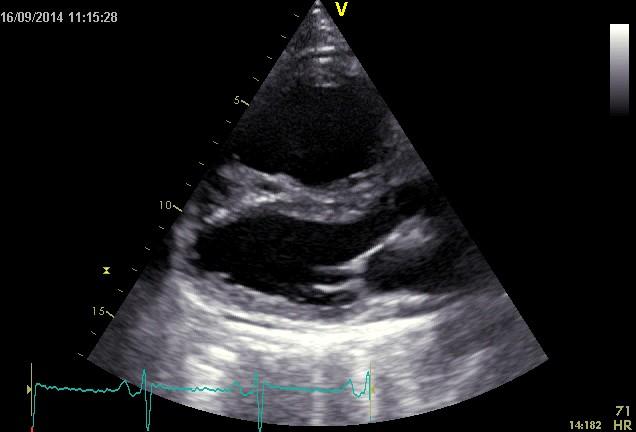

Echokardiografie: LEVÁ KOMORA bez dilatace a hypertrofie, s normální systolickou funkcí a regionální kinetikou kromě D shape, EF LK 55-60%. Diastolická funkce: porucha relaxace LK. PRAVÁ KOMORA FAC PK 18%, TAPSE 13 mm, Vt 9 cm/s, dilatace a hypertrofie PK, těžká prekapilární PH, odhadovaný PASP 90 mmHg, MPAP 55 mmHg, malý perikardiální výpotek

Echokardiografie: LEVÁ KOMORA bez dilatace a hypertrofie, s normální systolickou funkcí a regionální kinetikou kromě D shape, EF LK 55-60%. Diastolická funkce: porucha relaxace LK. PRAVÁ KOMORA FAC PK 19%, TAPSE 17 mm, Vt 9 cm/s, dilatace a hypertrofie PK, těžká prekapilární PH, odhadovaný PASP 130

mmHg, perikardiální výpotek